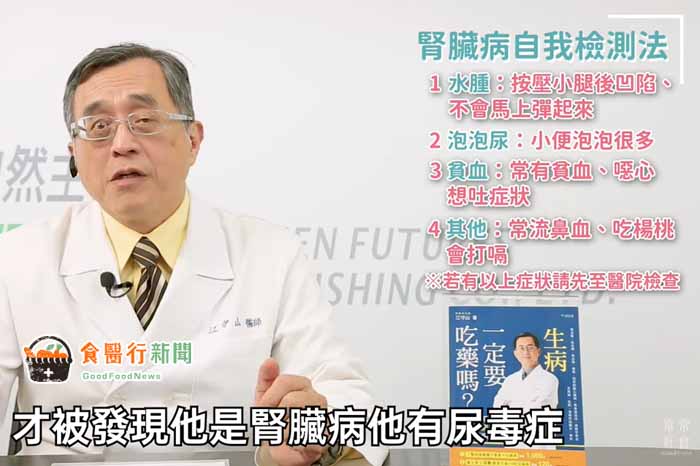

★腎臟病自我檢測法:水腫、泡泡尿、貧血、其他